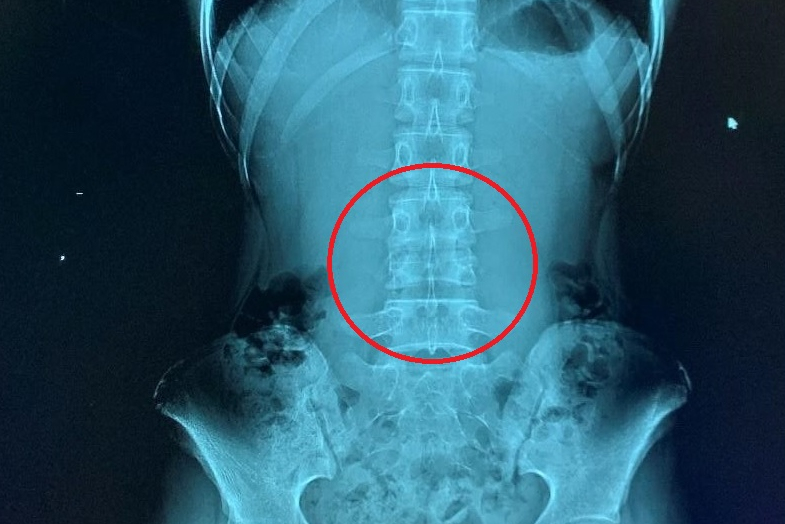

The dielectric effect is seen when using higher magnetic field strengths, typically 3T or more, and occurs when the radiofrequency wavelength is of similar magnitude or smaller than the patient's cross-sectional diameter, leading to constructive and destructive interference patterns and hence, areas of increased or decreased signal intensity.

At a field strength of 3T, the radiofrequency wavelength is 26 cm, which may be smaller than the abdominal diameter, particularly in patients with obesity, ascites, or pregnancy. "Central decreased intensity can obscure pathology," they concluded.